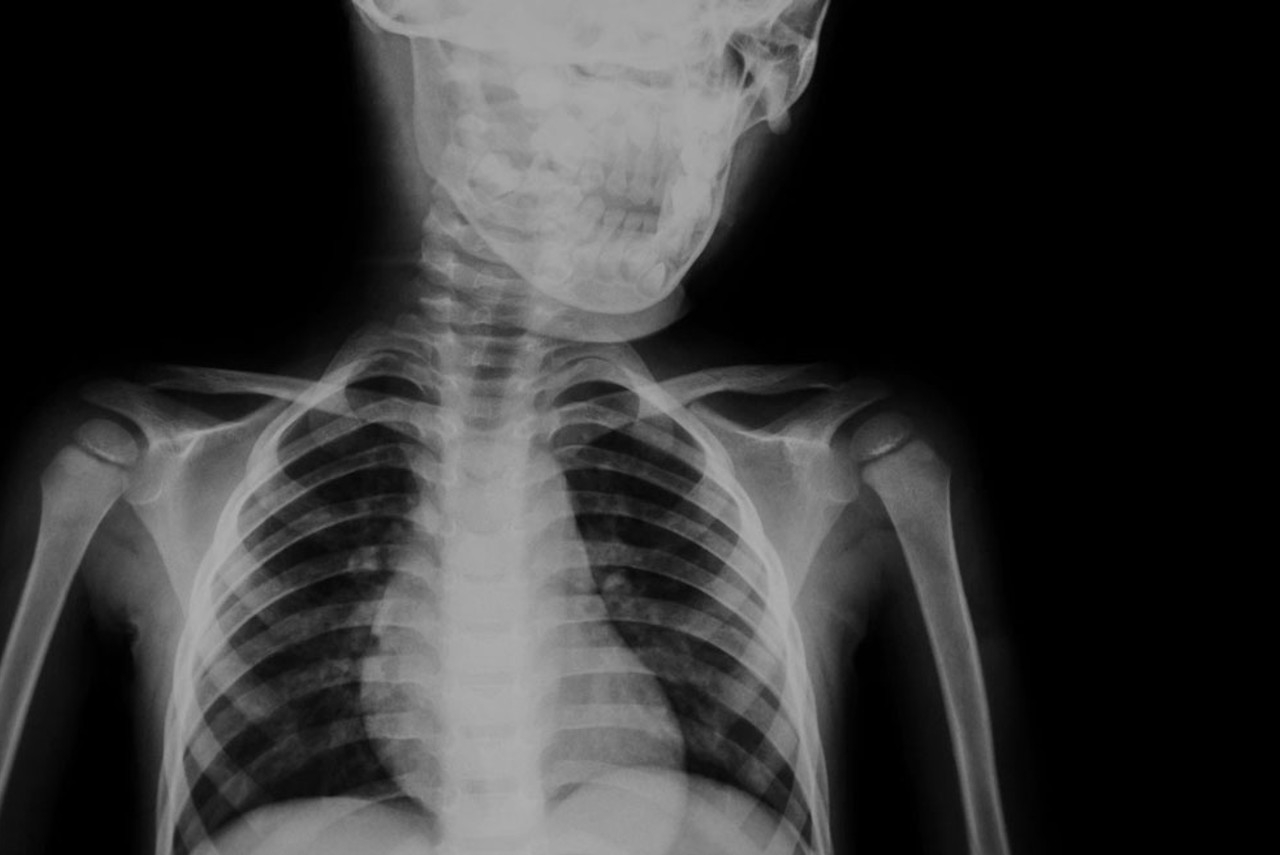

An x-ray image is created when a small amount radiation is passed through a body part. Different internal structures absorb different amounts of radiation, which is why the end result of an x-ray shows the white solid bone structures and grey muscle areas.

X-ray is the most common form of medical imaging. In order to receive an x-ray you will need a referral from a medical practitioner. At Queensland X-Ray, you do not need an appointment for an x-ray. Just visit us at your local practice.

There are several reasons why your doctor may have referred you for an x-ray. These reasons may include:

- Broken or fractured bones

- Diagnosis of arthritis in the joints

- Diagnosis of chest and lung conditions such as pneumonia